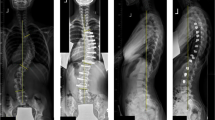

Deformity in adolescent thoracic spine has high prevalence worldwide. The objective of this work was to study the biomechanical behavior on the thoracic spines of adolescents under asymmetric ligament load in kyphosis and rectified kyphosis. Two finite element models of an adolescent thoracic segment, T5–T10, were generated with every bone component, intervertebral discs, the flavum, intertransverse and supraspinous ligaments. The three-dimensional geometry of the T5-T10 was generated with Autodesk®Maya®, and HyperMesh® version 14.0 was used to generate the finite element models. Asymmetric ligament load of 10 N was applied in the T8–T9, with and without axial load of 400 N in the T5 vertebra. Rectified kyphosis showed the highest rotational displacement of the T8–T9 unit: 0.16° with axial load and asymmetric ligament load, and 0.22° with asymmetric ligament load alone. Kyphosis exhibited rotational displacement of 0.11° and 0.12°, respectively, for the same load conditions. Rectified kyphosis subjected to an asymmetric ligament force showed greater inoperability of the facet joints, and therefore greater vulnerability to vertebral rotation. The results suggest the need for greater attention to the vertebral assessments in the sagittal plane, beginning from the growth spurt period, to adopt preventive therapeutic in vertebral deformities such as adolescent idiopathic scoliosis.